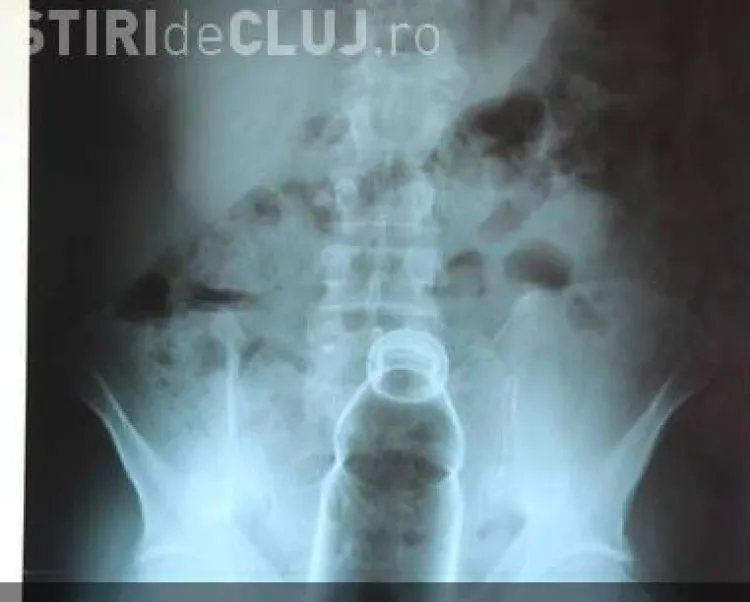

Medicii de la urgență au făcut un șoc când au primit un pacient de 46 de ani care avea o sticlă de suc de 500 de mililitri în anus.

Pacientul din judeţul Botoşani s-a prezentat la Spitalul Judeţean Suceava unde i-a fost făcută o radiografie, iar apoi a fost operat pentru a i se scoate sticla de suc din fund.

După ce și-a dat seama că sticla i-a rămas blocată în anus, bărbatul s-a prezentat la spital, unde le-a povestit medicilor situația. S-a intervenit chirurgical, s-a extras corpul străin, iar pacientul se află într-o stare bună, se recuperează. În prezent, pacientul este internat în Secţia de chirurgie a spitalului şi, probabil, perioada de spitalizare va mai dura câteva zile”, a explicat purtătorul de cuvânt al Spitalului Judeţean Suceava, doctorul Tiberius Brădăţan.